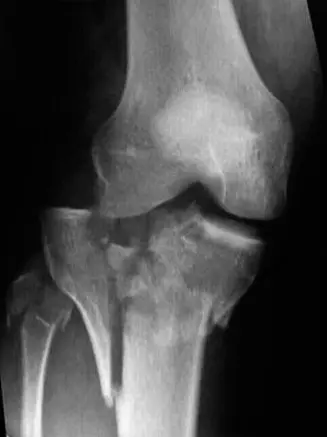

صورة توضيحية لـ كسر هضبة الظنبوب من النوع السادس: دليل شامل للتشخيص والعلاج والتعافي مع الأستاذ الدكتور محمد هطيف في صنعاء

أ. الأشعة السينية (Plain Radiographs)

• الاستخدام: هي الخطوة الأولى في التصوير. يتم التقاط صور للركبة المصابة من زوايا مختلفة (أمامية خلفية AP، جانبية Lateral، ومائلة Oblique).

• ماذا تظهر:

• المنظر الأمامي الخلفي (AP View): يكشف عن تفتت شديد في كلتا لقمتي الظنبوب (الداخلية والخارجية)، انخفاض في السطح المفصلي، واتساع في عرض الهضبة.

• المنظر الجانبي (Lateral View): يوضح الكسور متعددة الأجزاء التي تمتد إلى منطقة ما فوق المفصل (Metaphysis)، مع إزاحة خلفية لجزء كبير من الهضبة وانخفاض في السطح المفصلي.

• المناظر المائلة (Oblique Views): تساعد في تحديد مدى التفتت وتوجيه الشظايا، خاصة في الأجزاء الخلفية من اللقمتين.

• التصنيف الأولي: بناءً على الأشعة السينية، يمكن للأستاذ الدكتور محمد هطيف أن يشتبه في كسر هضبة الظنبوب من النوع السادس، الذي يتميز بانفصال الجزء المفصلي عن جسم العظم وتأثر كلتا اللقمتين.